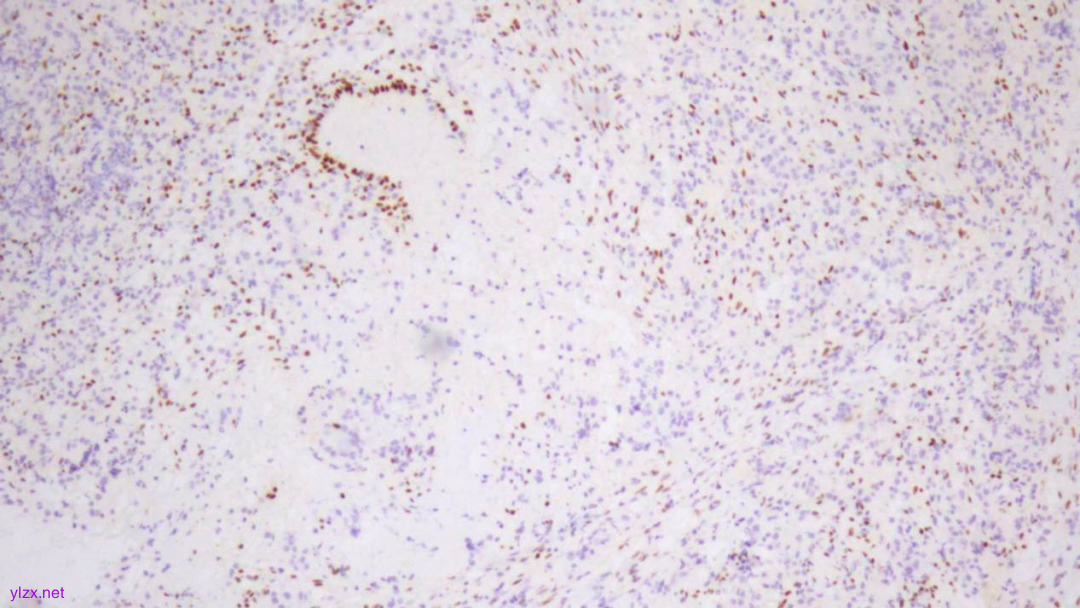

IHC结果:

P120(浆+),P16(灶+),P53(野生型表达),Her2(1+),CK7、GATA3、GCDFP-15、CK-H均(+),ER、PR、E-Cadherin、CK20均(-),Ki67(约5%+)

ER(-)

PR(-)

P120(+)

P120(部分+)

E-Cadherin(-)

GCDFP-15(弥漫+)

GATA-3(+)

CK7(弥漫强+)

Her2(1+)

Ki-67(散在+)